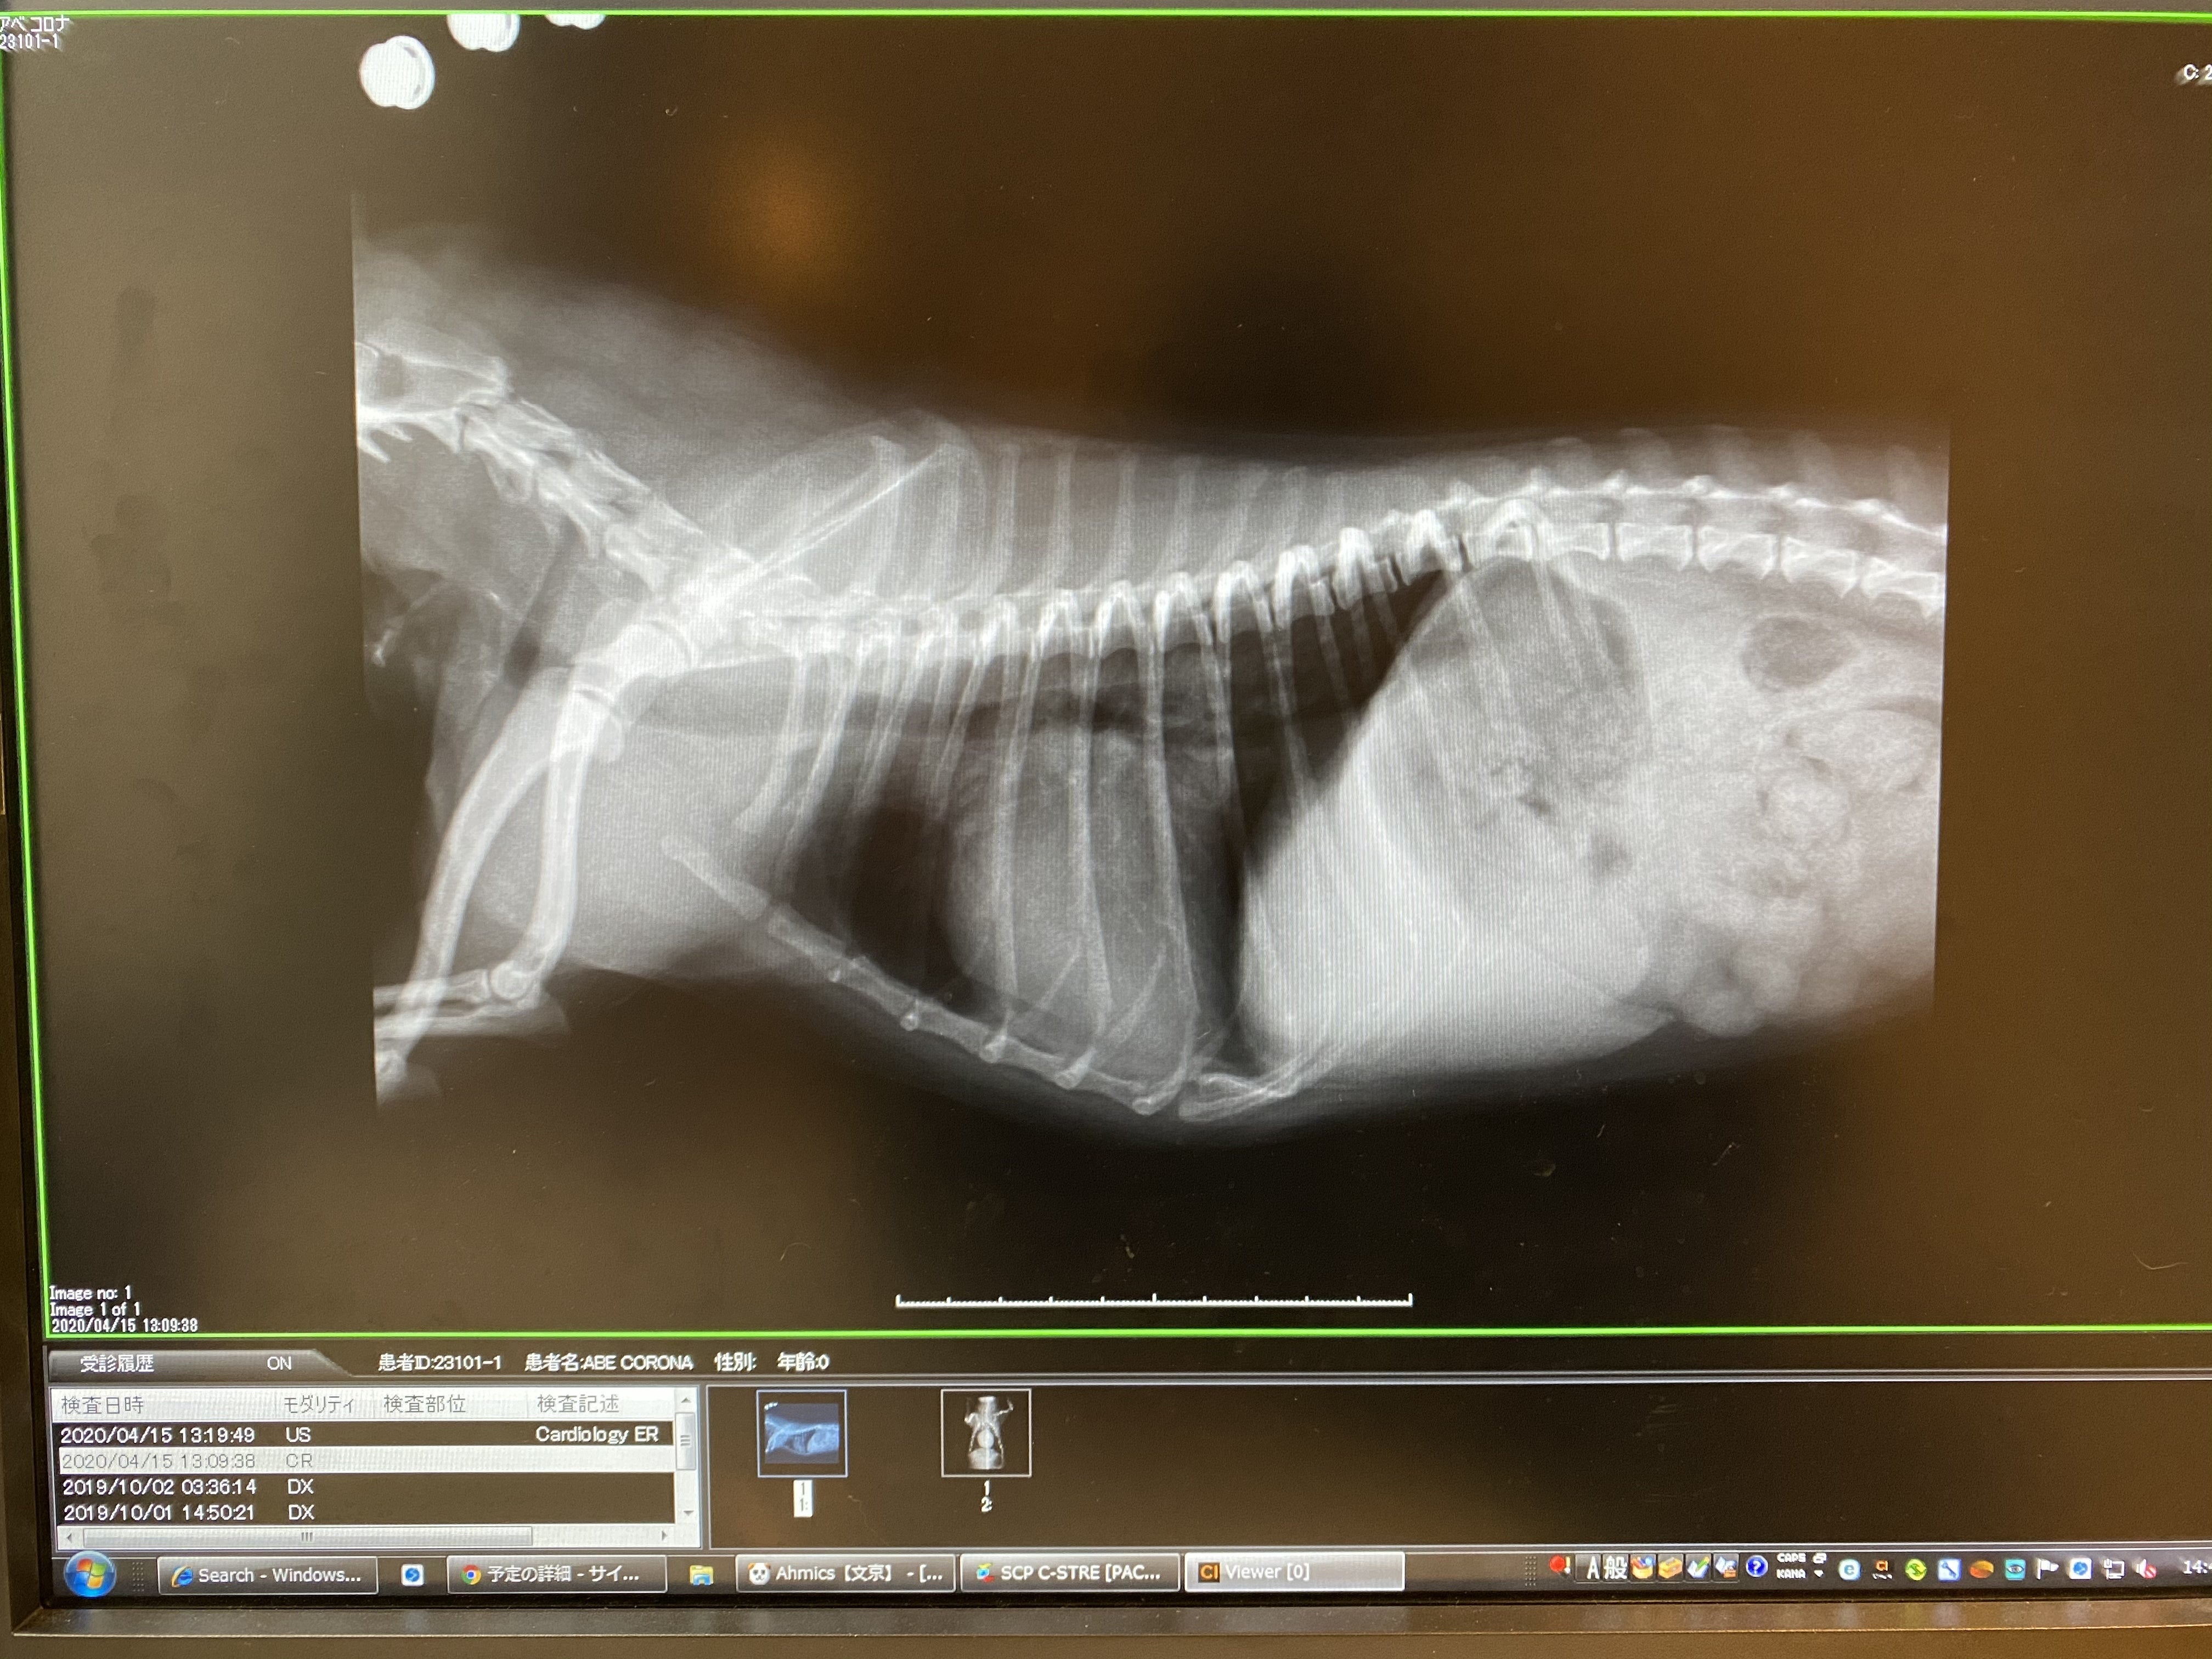

全身に血液が100%行き渡らず、心臓が血液を流そうと頑張りすぎて筋肉質になり肥大化しています。

真ん中の丸く膨れ上がってるのが心臓です

大きさは普通のチワワの2~3倍で、気道を圧迫していて苦しそうに咳をします。

心臓が気道を圧迫しているのが分かります

加えて逆流で左心房が限界まで膨れ上がると、行き場を失った血液が肺にまで浸み込み、肺が水浸しになる肺水腫を起こし、陸で溺れている状態の呼吸困難で最悪死に至ります。